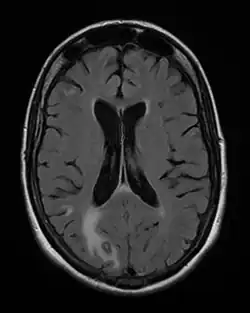

Toxoplasmosis in humans is diagnosed through biological, serological, histological, or molecular methods, or by some combination of the above.[62] Toxoplasmosis can be difficult to distinguish from several other conditions, especially ones that are common in HIV/AIDS and immunocompromised patients, and can cause central nervous system problems and brain lesions.[68] Toxoplasmosis is most commonly mistaken for primary central nervous system lymphoma, both conditions cause lesions in the brain, but in about 50-80% of cases the lesions appearances can be very similar on imaging, and exist in an area of the brain that makes biopsying too risky, however the main difference is lymphoma typically causes a single lesion in the subependymal region, and toxoplasmosis causes multiple lesions scattered through the basal ganglia.[69] Other conditions that can present as toxoplasmosis on a differential diagnosis are metastatic brain lesions, progressive multifocal leukoencephalopathy[70], CNS tuberculosis[71], bacterial or fungal brain abscess, cytomegalovirus (CMV),[72] and herpes simplex encephalitis.[68][73]

Lymph nodes affected by Toxoplasma have characteristic changes, including poorly demarcated reactive germinal centers, clusters of monocytoid B cells, and scattered epithelioid histiocytes.